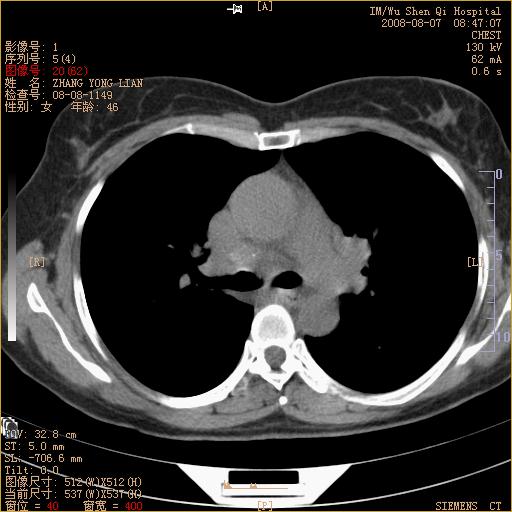

标题: CT15050:女,46岁,咳嗽胸痛一月余 [打印本页]

纵隔窗没发全,左下肺近胸膜处结节。有长毛刺,纵隔淋巴结增大,不排除恶性病变。

考虑左肺下叶后基底段周围型肺癌伴纵隔淋巴结转移可能性大。

左下肺ca并纵隔及左肺门区淋巴结转移。

1)考虑左肺下叶后基底段周围型肺癌伴纵隔淋巴结转移。2)脾内低密度灶,性质待定;不排除转移瘤可能。